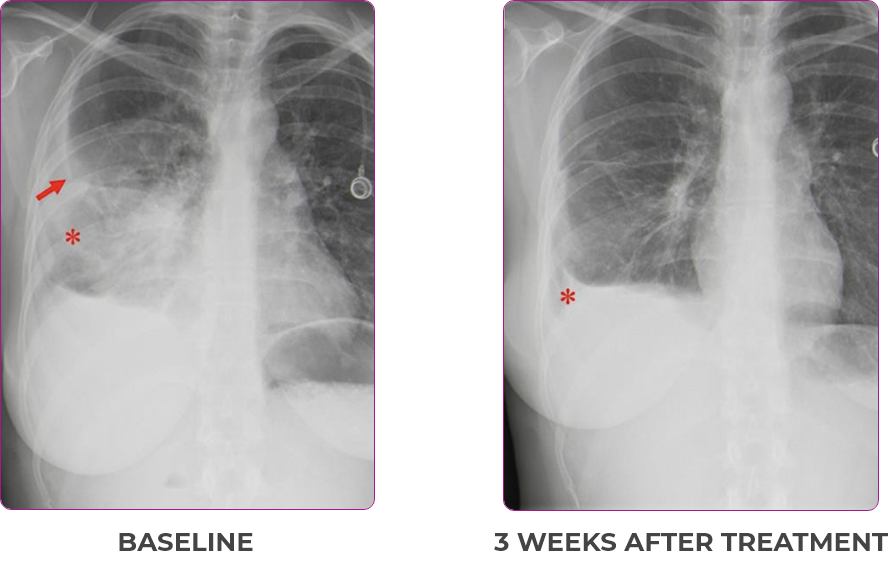

Response in primary and metastatic lesions1

Lung imaging of primary tumors.

SCAN 1: LUNG

SCAN 2: LUNG AND BONE

Response to VITRAKVI1

- Partial response and symptom improvement confirmed by chest X-rays after <1 month of treatment

- Imaging performed 6 weeks into treatment revealed considerable decrease in the size of both target lesions

- No treatment-related AEsa were reported

- Complete clinical response achieved by 12 months with residual scarring

- Patient was symptom free and remained on VITRAKVI